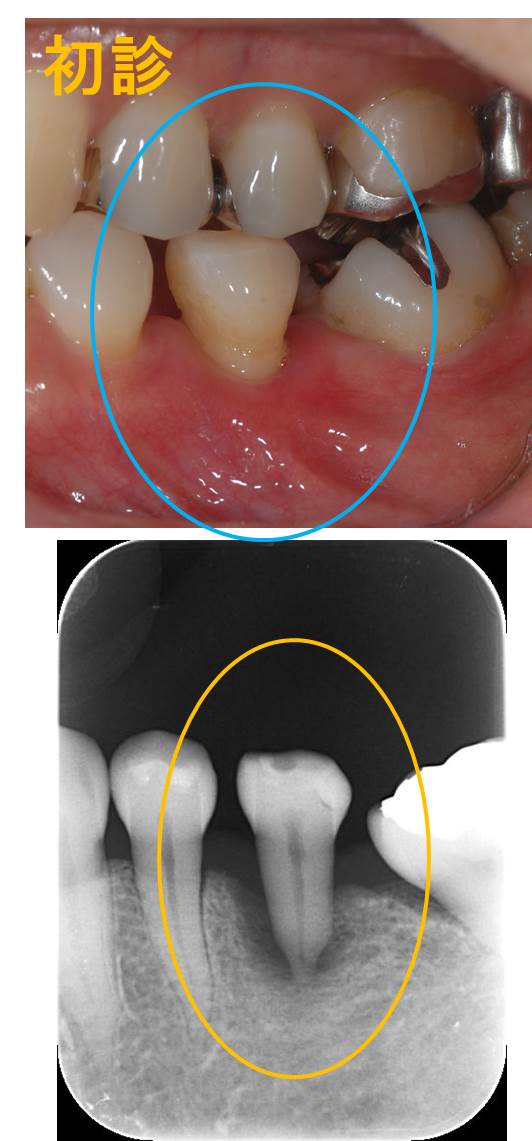

今回は、重度歯周炎の骨再生が認められたケースを紹介します。

歯槽骨が根尖(根の先)まで吸収してしまい、大きな動揺が観察されます。プロービングデプス(歯周ポケットの深さ)は7mm以上と深いです。そして生活歯(神経のある歯)です。

他の歯は問題なく、当該歯のみが重度歯周炎に罹患しています。

普通であれば抜歯のケースですが、1歯のみ重度であるため何か局所に加わる炎症性因子と外傷性因子が考えられ、またその他の環境因子が関係しているように思われます。

まず、付着歯肉がないことが大きな問題と考えました。要は、歯の周りを囲む「動かない歯茎」がほとんど無いことが問題を引き起こす環境因子になっているということです。